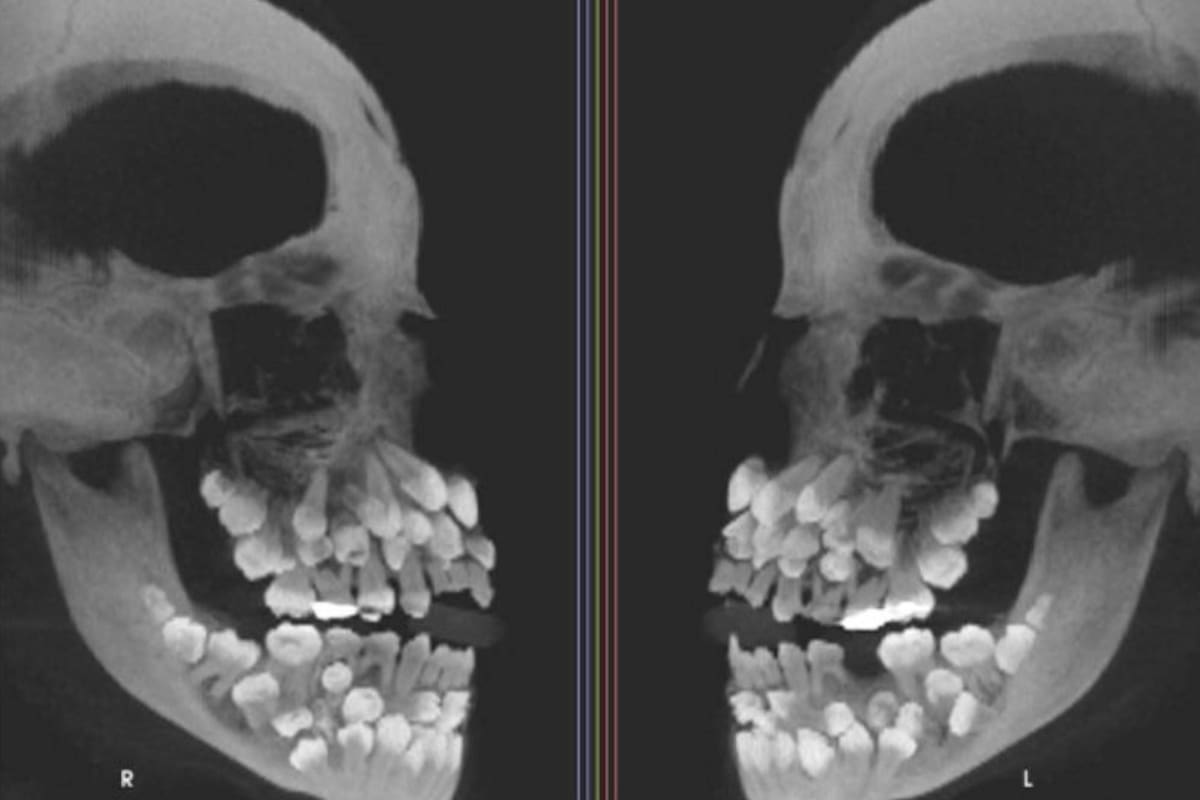

Una de las imágenes que exhibe el informe sobre este inusual caso es una tomografía computada de haz cónico (CBCT) tomada desde los dos laterales del rostro de la pequeña. Allí se ve, en blanco sobre negro, la exagerada cantidad de piezas dentales con las que cuenta esta paciente, que asemejan a un ramillete de dientes distribuidos tanto en el maxilar superior como en la mandíbula.

Una niña de 11 años acudió al dentista por padecer una afección llamada “hiperdoncia múltiple”. Esto es, tenía muchas más piezas dentarias de las 32 que habitualmente tienen las personas. Luego de que se le realizara una tomografía computarizada, los especialistas descubrieron con gran asombro que la pequeña contaba nada menos que con 81 dientes.

De estas 81 piezas, los especialistas establecieron que 18 eran dientes caducos, 32 permanentes y 31 supernumerarios o múltiples. Estos últimos representa una infrecuente anomalía del desarrollo de la cavidad bucal, pueden aparecer en cualquier zona de la arcada dentaria y afectar cualquier órgano dental, señalaron los especialistas.